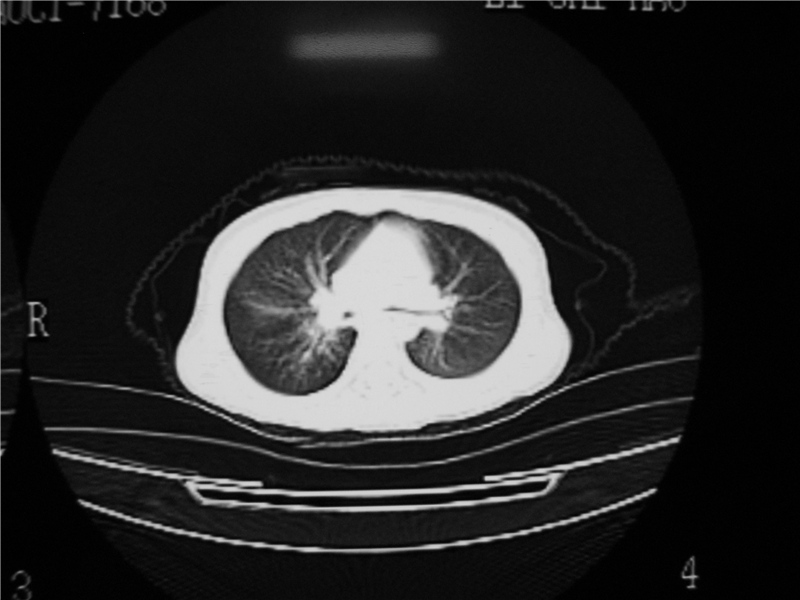

标题: PED3236:男2岁进食花生米后发烧10天。

右肺中叶及下叶内段大片实变密度增高影,可见支气管气象,肺炎.

摄吸气及呼气相对比片,本例为有肺中叶阻塞性炎症、不张,右肺下叶阻塞性炎症。

1)右肺炎症并右肺中叶肺不张,右肺上叶充气不良。2)右侧支气管异物不排除。

结合病史,考虑气管异物所致。

结合临床考虑支气管异物并阻塞性肺炎、肺不张。